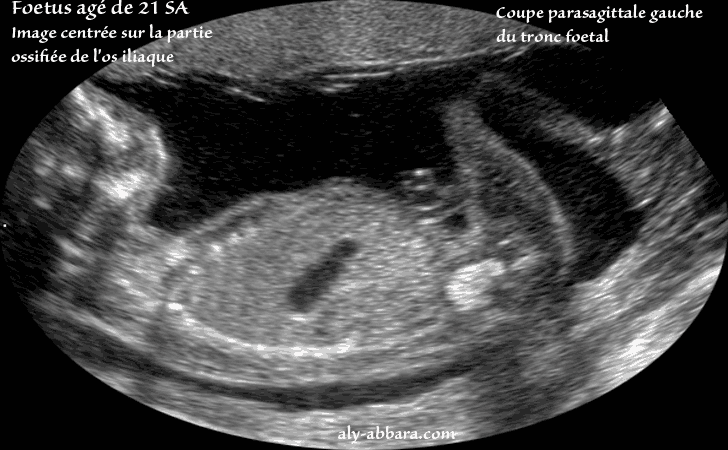

Image échographique centrée sur la partie ossifiée de l'os iliaque gauche

Il s'agit d'une coupe para-sagittale gauche du tronc chez un fœtus âgé de 21 semaines d'aménorrhée.

A ne pas confondre avec une hyperdensité intestinale